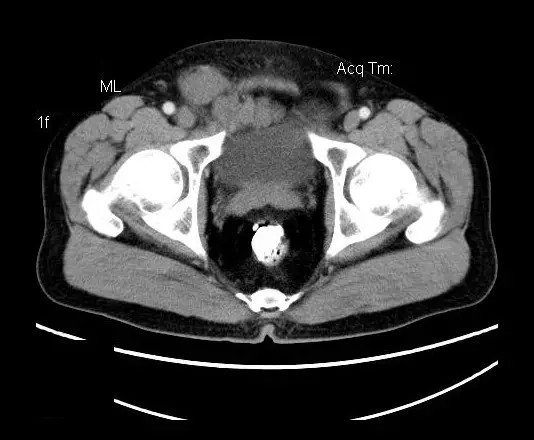

【影像表现】

盆腔右前侧及邻近腹股沟区可见多发大小不等的聚集生长的结节影,病灶呈软组织密度,边缘尚规整,分界尚清,增强扫描可见不均匀强化。膀胱局部受压,盆腔未见明显肿大淋巴结影。

“盆腔”多发性神经鞘瘤